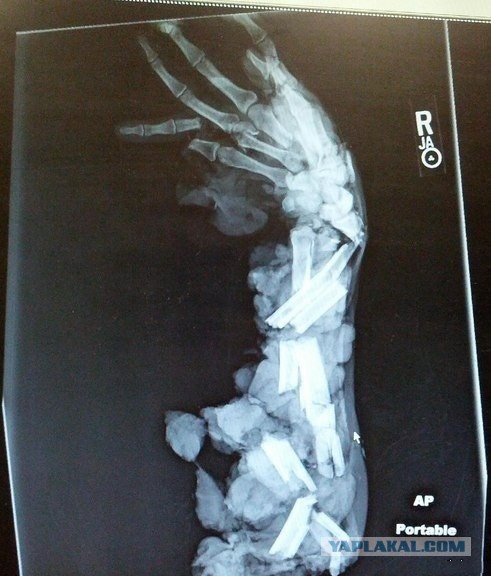

Посоветуйте мазь, чтобы быстрее зажило